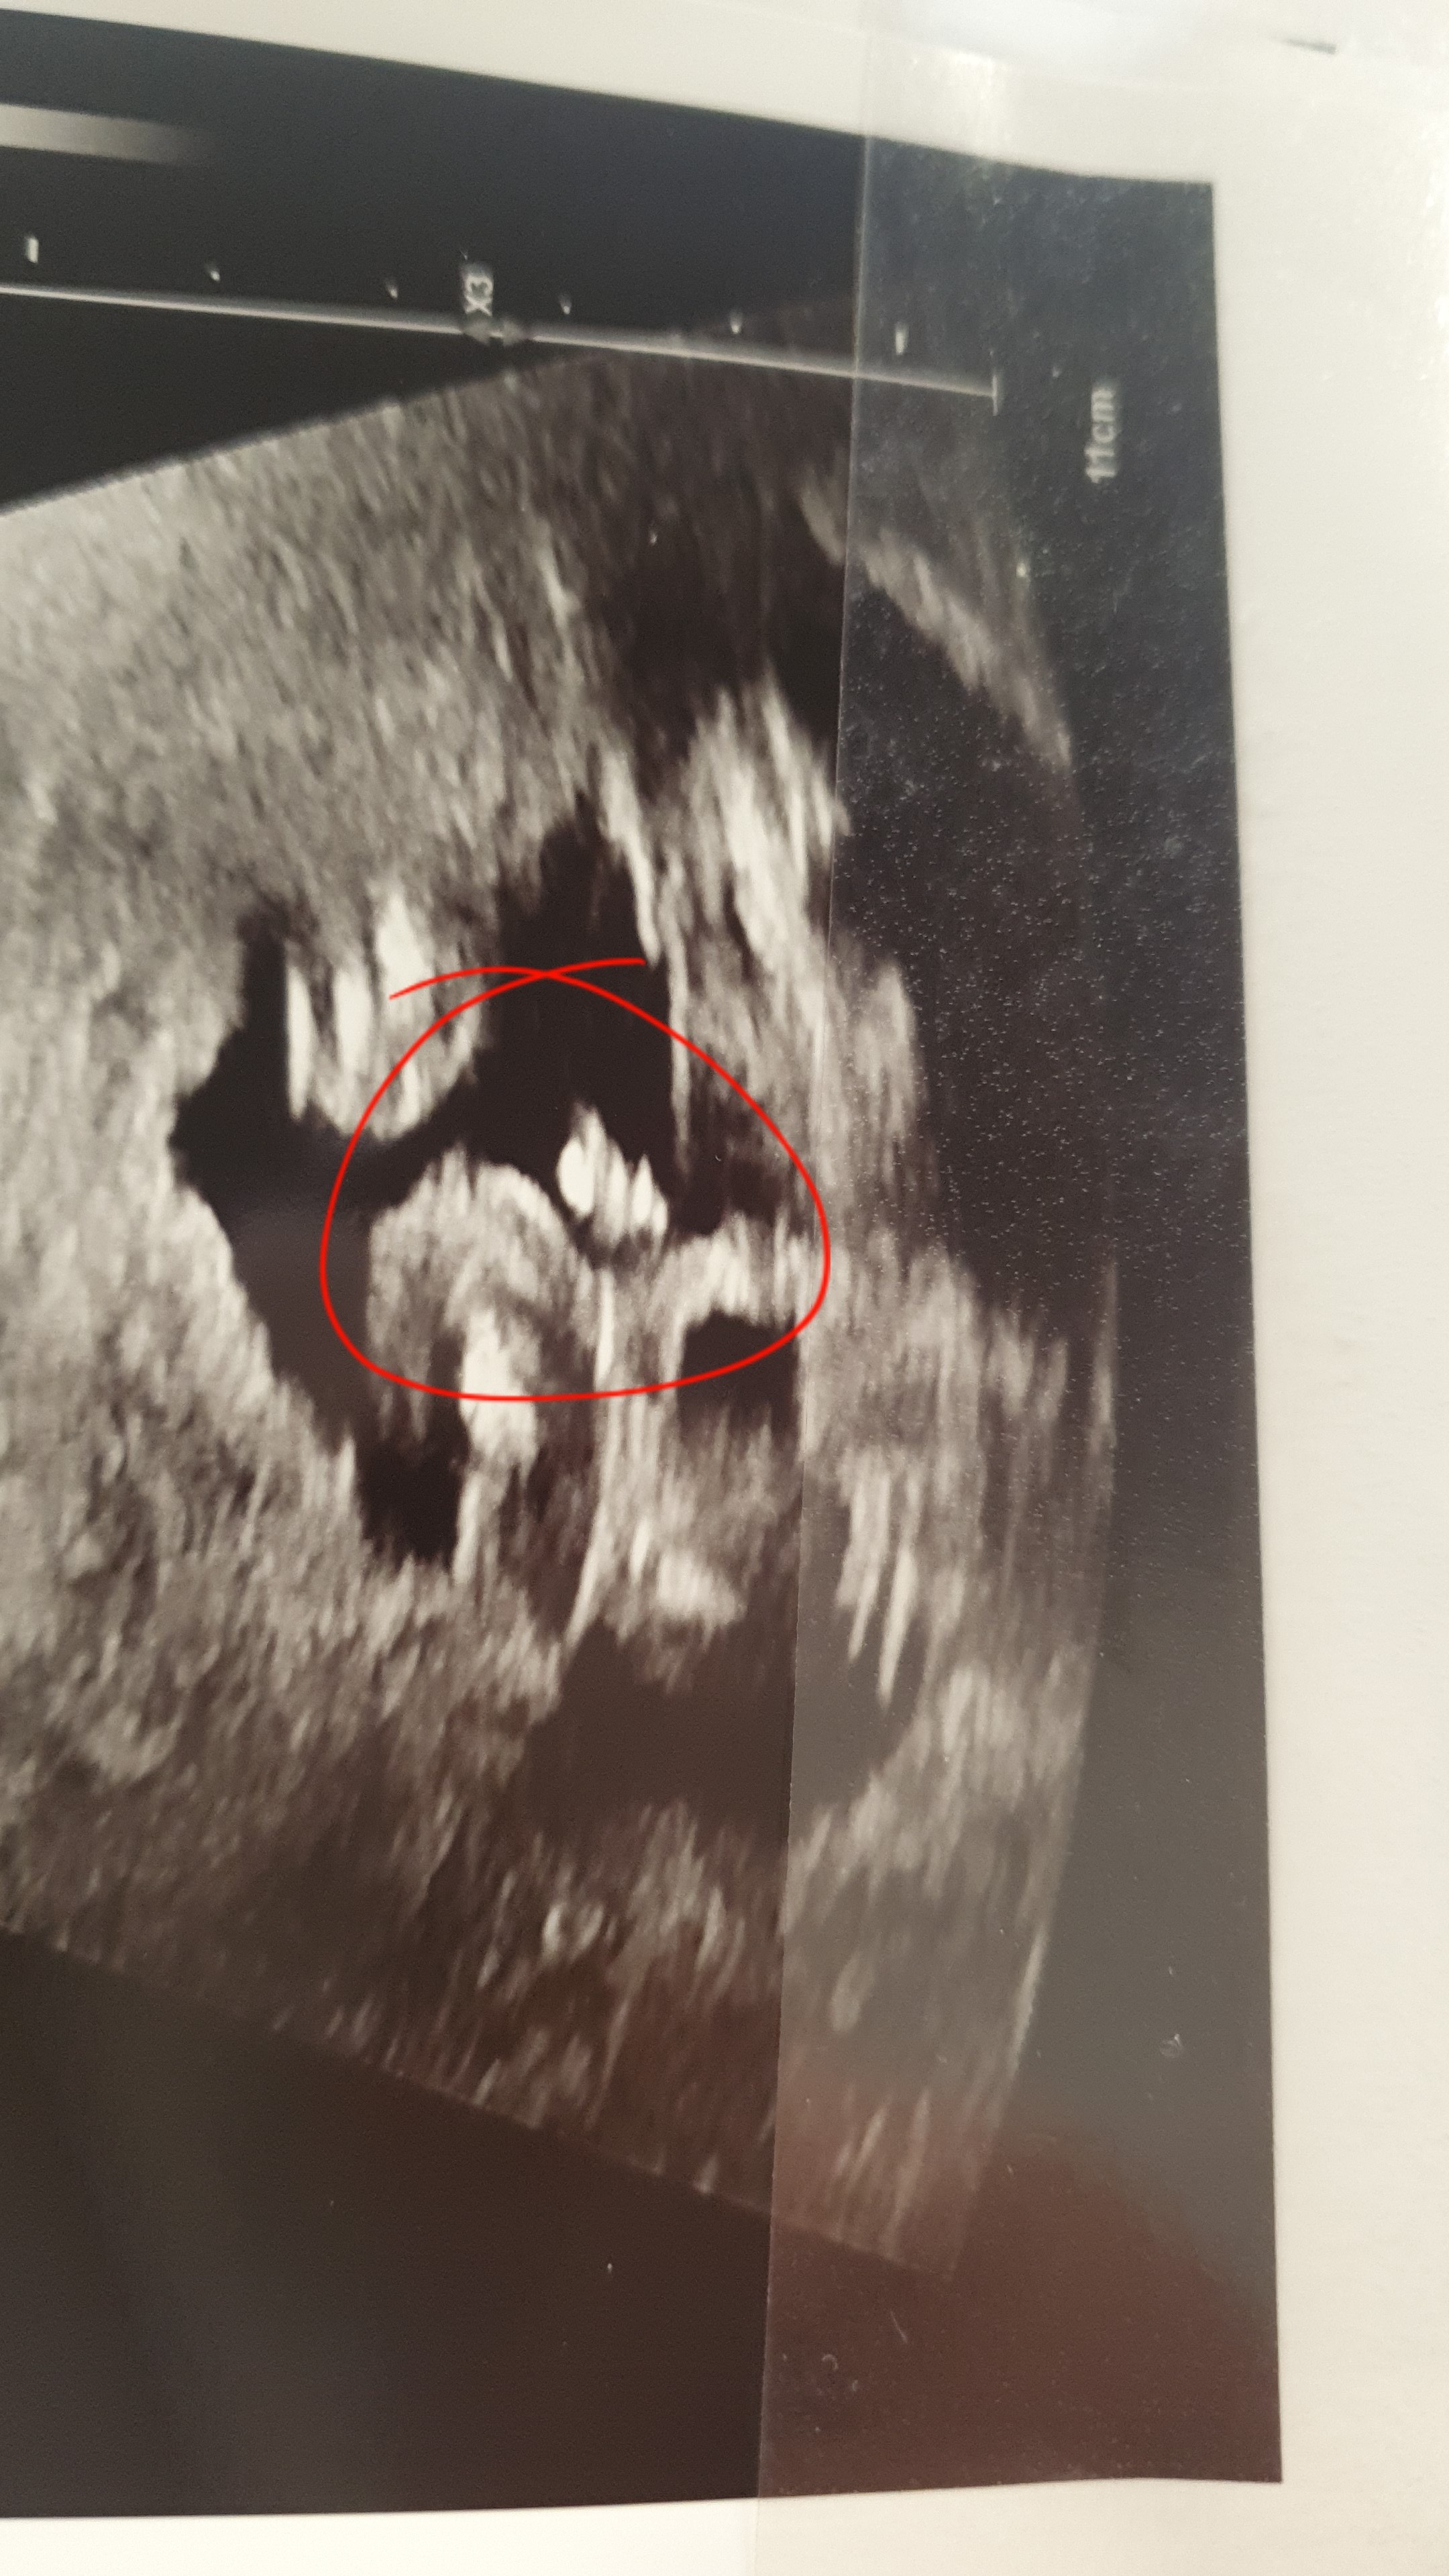

Powiedzcie mi proszę czy wy u mojej kruszynki widzicie siusiaka czy może pępowinę?

Co do USG nie pomogę, kiepska jestem z odczytu obrazu USG, na zdjęciu które wkleiłaś to w ogóle nie wiem gdzie co jest ;)